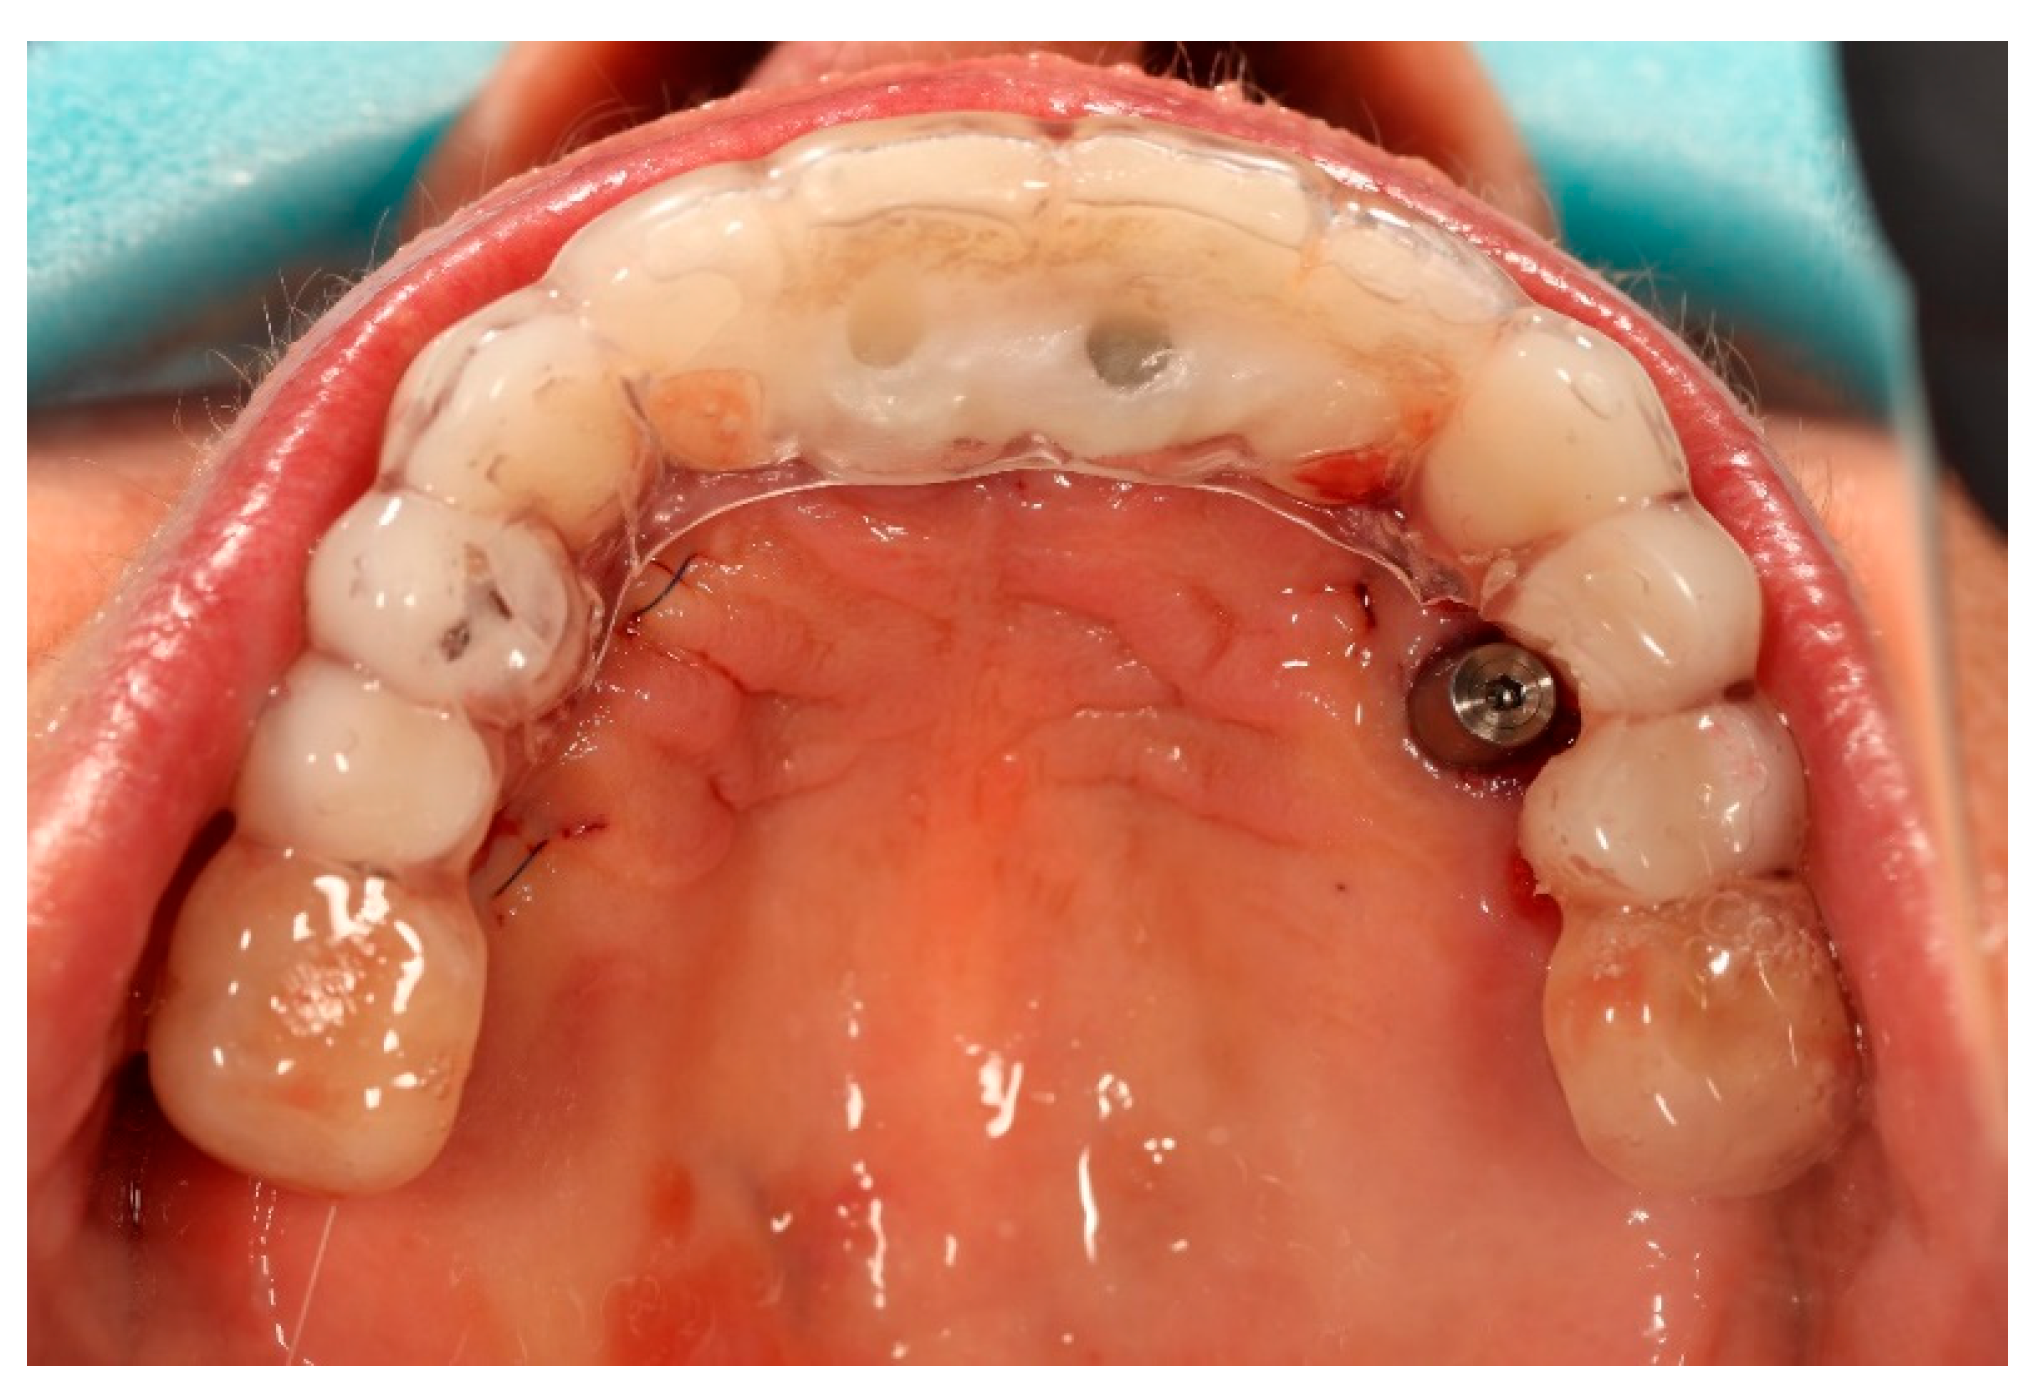

The surgical procedure was performed under local anaesthesia. In the first stage, teeth 13, 14, 23, 24, and 25 were atraumatically extracted. Immediately thereafter, two ICX Active implants (diameter 3.75 mm, length 12.5 mm) (ICX-Implant System; Medentis Medical GmbH, Bad Neuenahr-Ahrweiler, Germany) were inserted into the post-extraction sockets in positions 14 and 24. Excellent primary stability exceeding 35 Ncm was achieved for both implants. Two ICX Active implants were placed following the manufacturer’s drilling protocol, adapted to the clinical conditions of the post-extraction sockets (Figure 3).

At the end of the procedure, the transparent acrylic splint was fixed on the remaining prosthetic restorations, ensuring that no contact or pressure was applied to the healing screws at positions 14 and 24 (Figure 6 and Figure 7).

Figure 3. Remaining prosthetic restorations still in place, with visible post-extraction sockets and the two immediately placed implants in positions 14 and 24.